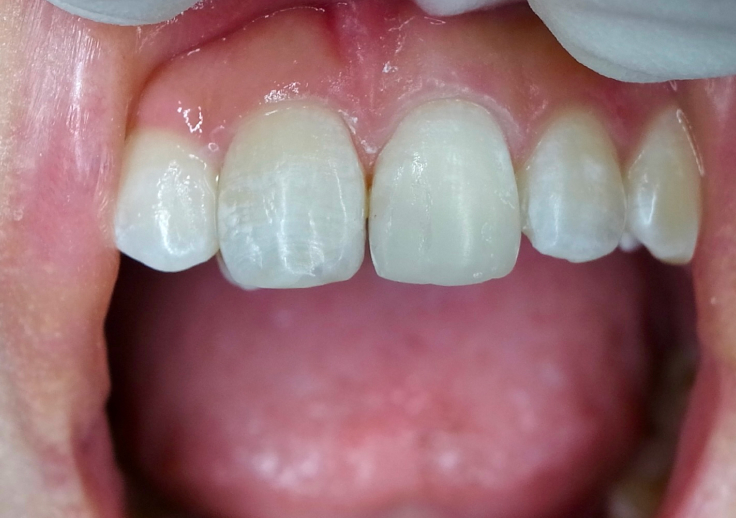

Before

After